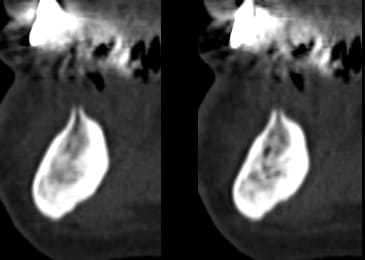

Un nouveau cas à étudier, merci du cadeau Béotien

Des avis?

sur un opt , c'est pas top pour voir quoi faire.

un ptit scan ?

> La démo super bien menée sur un cas bcp plus difficile à gérer

> qu'il y paraissait

> Beaucoup de calme et de sureté et d'humour,dans les moments difficiles et il y

> en a eu, même avec la technique d'expansion condensation les 2 artérioles ont

> essayé de l'embêter, les tables vesti en regard 42 et 32 aussi

> au final 4 implants enfouis et bloqués

> travail très propre et j'ai beaucoup appris

mais je n'aurai du ecouter que mon coeur et en mettre un 5° en 33 ce serait plus joli sur le pano